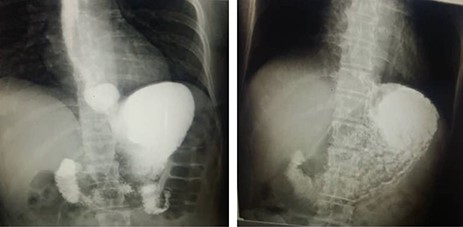

A 38-month-old girl was admitted with 2-week history of epigastric pain and 10-day history of appetite loss. Labs showed normal CBC with a slight anaemia (Hb: 11.9 g/dl). Endoscopy showed a displacement of the LES with a stricture in the lower third. The barium meal showed the abdominal viscera protruding into the chest with left mediastinal displacement (see Fig. 3). Open surgery showed stomach protrusion into the thoracic cavity which was fixed in the abdominal cavity with diaphragm repair.

Upper left photo is of case two that shows a barium swallow with 5.5 cm hiatus hernia. The upper right photo is of case 4 that shows a barium swallow with 8 cm hiatus hernia. Lower 2 photos are of case 3 that show barium swallow with a 6 cm hiatus hernia.

An 18-month-old boy was admitted to the Children Hospital with a 3-week history of progressive pallor and 1 day history of melena after which his parents brought him to a private clinic when a chest X-ray showed that he had HH with the stomach being in the chest cavity with an enlarged left pulmonary hilum and right mediastinum displacements (see Fig. 3). CBC showed that he was also severely anaemic (Hb: 6 g/dl). He reported no other symptoms and had not been prescribed any previous medications. An endoscopy was performed which showed an abnormal location of the stomach in the thoracic cavity. The barium meal was obtained which confirmed the HH. In open surgery from the abdomen, the stomach and the oesophageal hiatus were found to be herniated into the thoracic cavity. They were repaired with Nissen surgery.

An 8-month-old boy was admitted with a 20-day history of black, loose diarrhoea (5–6 occurrences in total) with no frank blood in the stool. He had low fever. Lab tests were normal with positive stool occult blood test. Following symptomatic treatment for 2 weeks, an endoscopy was conducted which showed a displacement of the LES with mild lower ulcerative oesophagitis and was confirmed later on with a plain X-ray and a barium meal to be an 8 cm HH (see Fig. 3). The HH was repaired with Nissen open surgery.